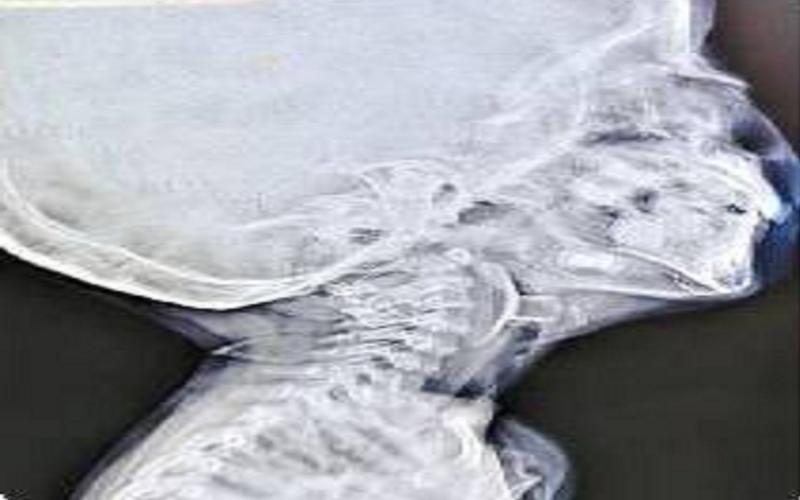

भिलाई (खबरगली) भिलाई स्टील प्लांट (बीएसपी) के सेक्टर-9 अस्पताल में डॉक्टरों की तत्परता और टीम वर्क ने एक तीन वर्षीय बच्चे की जान बचा ली। बच्चे के वोकल कॉर्ड (स्वर यंत्र) में खिलौने का एक हिस्सा फंस जाने से उसकी सांस अचानक रुक गई थी। परिवार घबराए हुए हालत में उसे अस्पताल लेकर पहुंचे, जहां हर सेकंड उसकी जिंदगी के लिए कीमती साबित हो रहा था।